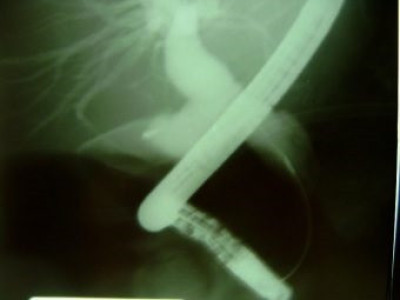

Quiste de coledoco tipo II

Envíado por Dr. Carlos Miguel Zavaleta Consuegra